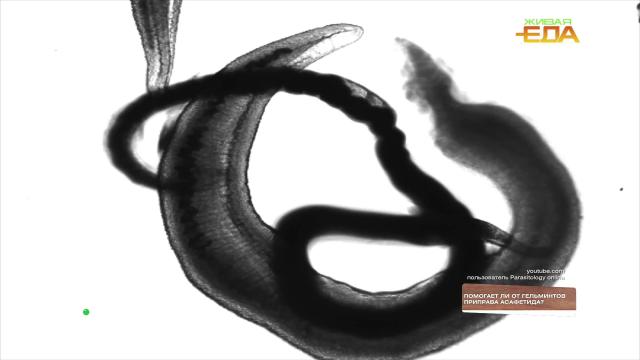

Гельминты или глисты — это черви, которые могут паразитировать в органах и тканях человека и вызывать очень неприятные болезни. В разных частях света преобладают разные их виды, и везде пытаются применять разные народные средства. Одни из самых популярных в России — чеснок, теплое молоко, семена тыквы.

А в Индии предпочитают использовать асафетиду — многолетнее травянистое растение рода ферула. Ее используют как приправу, которая по вкусу напоминает смесь лука и чеснока, поэтому в странах, где она популярна, ею заменяют эти специи. Ученые из Египта в опытах на мышах обнаружили, что асафетида в виде порошка активно борется с возбудителем кишечного шистосомоза. А иранское исследование показало, что экстракты асафетиды и чеснока оказывают отравляющее действие на личиночные стадии круглых червей. Также антипаразитарное действие чеснока было доказано на мышах и рыбках гуппи — пока не на человеке.